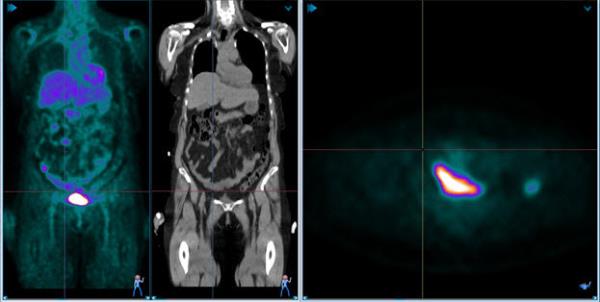

PET-C fusion view